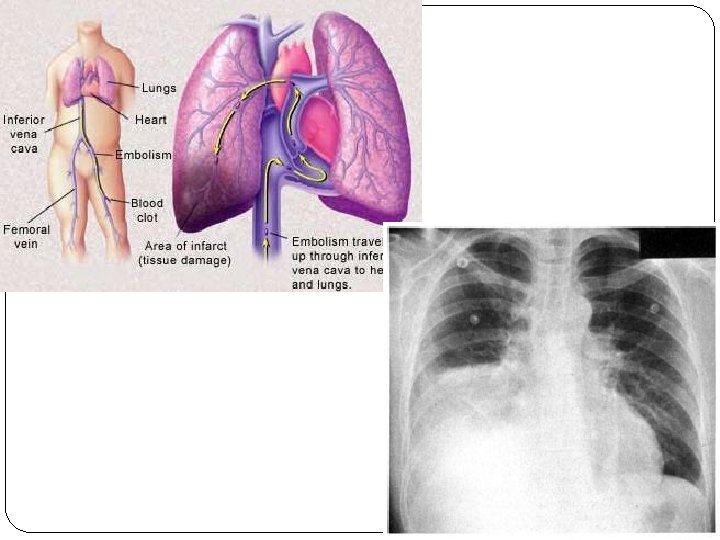

Deep Venous Thrombosis = Phlebothrombosis + it´s most dangerous complication = pulmonary embolisation (PE) – belong (after IHD and hypertension) among the most common CV diseases in hospitalised patients PE - 10% of autopsial material 85% of PE is caused by deep venous thrombosis

PHLEBOTHROMBOSIS (PT) deep veins of lower extremities primarily obturation of vein with thrombus and secondarily inflammatory reaction released thrombus = embolus clinically: often asymptomatic – or little symptoms = dg. only 30 -50% oedema – asymmetric pain – spontaneous, compressive – mostly while hanging down the limb, spasms, feeling of strain symptoms of blocked blood flow from the limb (erythema- pale skin- cyanosis) collaterals –forming after several days of obturation as compensatory mechanism, systemic symptoms – not specific (if there is no PE)

Complications of PT 1. EMBOLUS - released thrombus, carried by the blood flow– mainly to pulmonary artery pulmonary embolisation 2. Repeated small embolisation (successive) =>chronic pulmonary hypertension => cor pulmonale chronicum 3. Chronic venous insufficiency